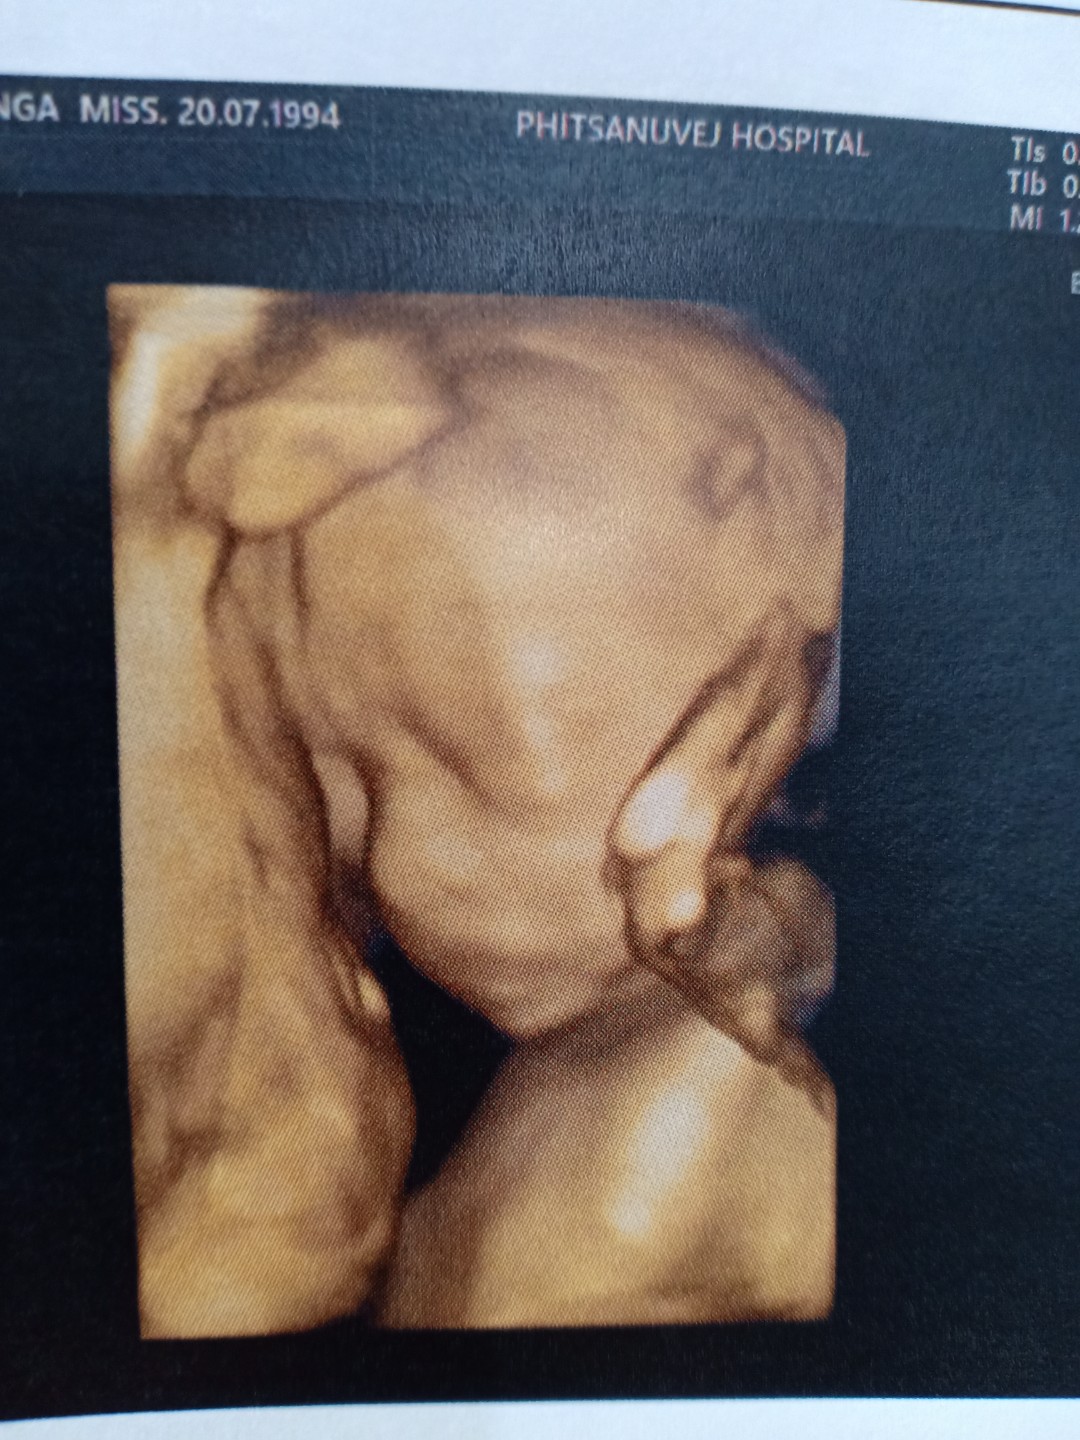

32wค่ะ